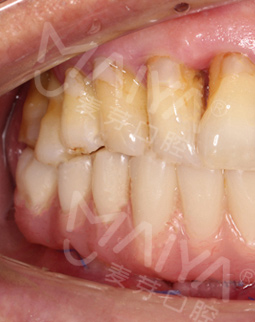

麦芽的博士专家团在看过我的片子后发现,我的牙齿由于长期对口腔疏于护理,牙周情况非常差,余牙有些松动,且牙槽骨萎缩严重,现存的骨量无法进行传统的种植牙手术,因此给我设计了“all-on-4”种牙技术的升级版本“all-on-5”,前期是要处理我的牙周问题,当天就给安排了洁牙,然后上药,等牙周恢复差不多就可以进行种植了!